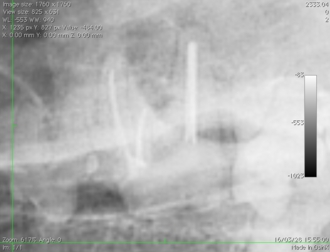

ポータブルレントゲンによる術中写真

術後の写真 充填( 赤ラインは根先部 )

麻酔なしのレントゲンにおいては2本が重なり一本に見えることもあります。